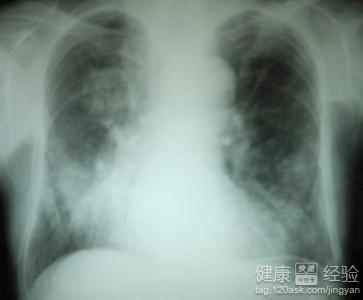

朋友20歲有些時候總感覺呼吸困難,咳嗽、咯痰和咯血 可干咳或有少量痰液,痰常呈白色泡沫樣漿液性,有時帶血,呈粉紅色泡沫痰。去醫院檢查治療後現有所好轉,現在與大家一起分享。